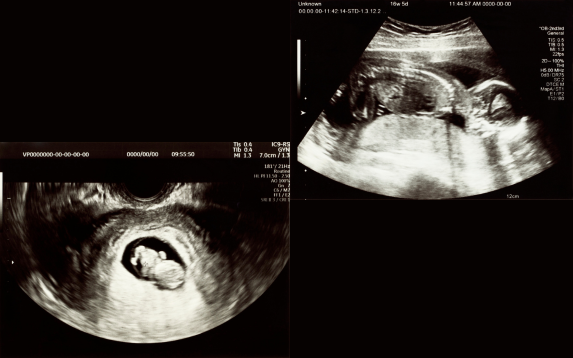

OB/GYN ultrasound is a vital imaging tool that helps assess women’s reproductive health and monitor pregnancy at every stage. Using safe, high-frequency sound waves, this procedure creates detailed images of the uterus, ovaries, fallopian tubes, cervix, and fetus. It helps detect abnormalities, confirm pregnancy, and evaluate fetal growth and development.

There are two main types of OB/GYN ultrasounds — transabdominal and transvaginal. A transabdominal ultrasound uses a probe on the surface of the abdomen, commonly during mid and late pregnancy. In contrast, a transvaginal ultrasound involves inserting a thin probe into the vagina for clearer imaging of the uterus and ovaries, especially in early pregnancy or gynecological evaluations.

During pregnancy, ultrasound scans are essential at different stages. The early scan confirms pregnancy and detects the heartbeat, while mid-trimester scans assess fetal anatomy, placenta location, and amniotic fluid levels. Later in pregnancy, growth scans monitor fetal position, weight, and overall well-being to ensure a healthy outcome for both mother and baby.

Advanced 3D and 4D ultrasound imaging provides real-time, high-definition visuals of the fetus and reproductive organs. These technologies enhance diagnostic accuracy and offer parents an emotional bonding experience with their baby through lifelike fetal images.